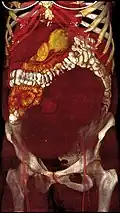

-

A very large (9 cm) fibroid of the uterus which is causing pelvic congestion syndrome as seen on CT -